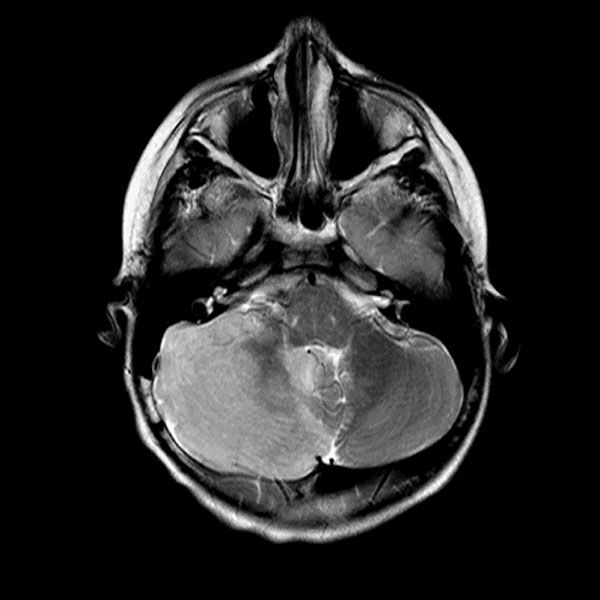

Urine toxicology, Tylenol level, Salicylate level, alcohol level thyroid studies, iron studies, hepatitis panel were normal. Urine pregnancy and COVID tests were negative. Head computed tomography (Head CT) showed mild hydrocephalus, and brain magnetic resonance imaging (MRI) showed increased signal folia and compression of the lower portion of the fourth ventricle and foramen of Magendie. She then had an emergency external ventricular drain placed (EVD) by pediatric neurosurgery, and the team started her on high-dose steroids and intravenous immunoglobulin (IVIG).

On the third day of admission, she developed new onset left-sided facial drooping, drooling, downbeat nystagmus, and difficulty following commands. An emergent subcortical craniectomy and decompression, duraplasty, and cerebellar biopsy were performed. A cerebellar biopsy was performed due to findings on brain MRI.

Consults were placed with pediatric neurology, pediatric infectious disease, pediatric hematology. Etiologies considered, included infectious, heavy metal poisoning, autoimmune, metabolic, and oncologic, with the following studies ordered: Cytomegalovirus Antibody(Ab) panel, and DNA, Coccidioides Ab, Epstein Barr Virus titers, fungal cerebrospinal fluid(CSF) panel, Human Immunodeficiency Virus testing, mycoplasma pneumoniae Ab, tuberculosis testing, toxoplasma Ab, meningitis panel, lactate dehydrogenase , uric acid, blood smear, CSF cytology, heavy metal panel, lead level, hemoglobin electrophoresis, complete blood count, complete metabolic panel, anti-nuclear Ab, N-Methyl-D-Aspartate receptor Ab, and ammonia. Lhermitte-Duclos disease versus cerebritis were also considered based on clinical status and radiological findings on brain MRI (Table 1).

Her biopsy result had nonspecific findings not consistent with Lhermitte-Duclos disease which is an extremely rare tumor of the cerebellum (dysplastic cerebellar gangliocytoma). The final diagnosis was lead encephalopathy.